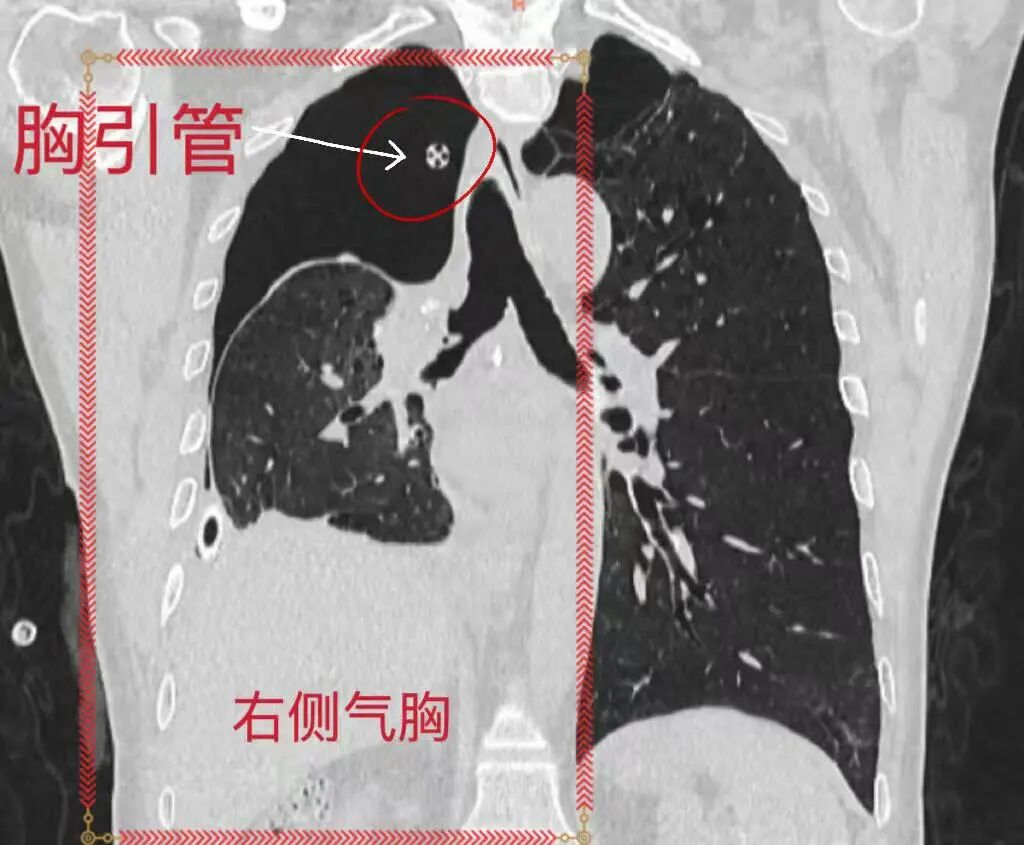

BPF封堵前右側氣胸持續引流

精準定位后,團隊通過內鏡分次注入混合生物制劑實施封堵,成功治愈多處瘺口。術后患者胸腔閉式引流瓶無氣體溢出,2根胸腔引流管先后順利拔除,恢復情況良好,復查胸部CT后康復出院,整個診療過程微創、安全、順暢。